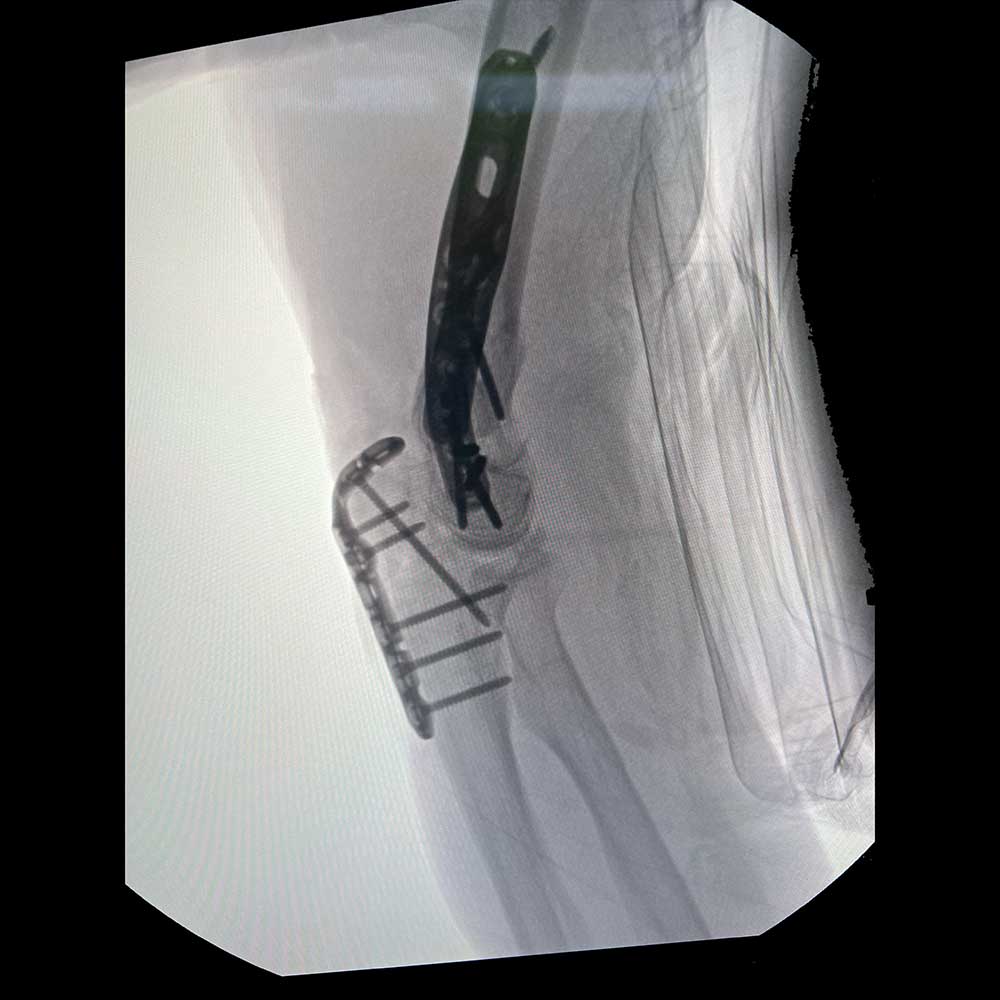

Periprosthetic Solutions

PLATING SYSTEM

- Only UE plating option that allows each same hole for:

- Screw placement

- Compression

- Screw lock into plate

- Cerclage Capability

- 40° Polyaxial locking

- Strong & consistent locking at every angle

- Titanium low-profile construct

- Compression before locking

- Polyaxial drill guides allow for provisional K-wire fixation